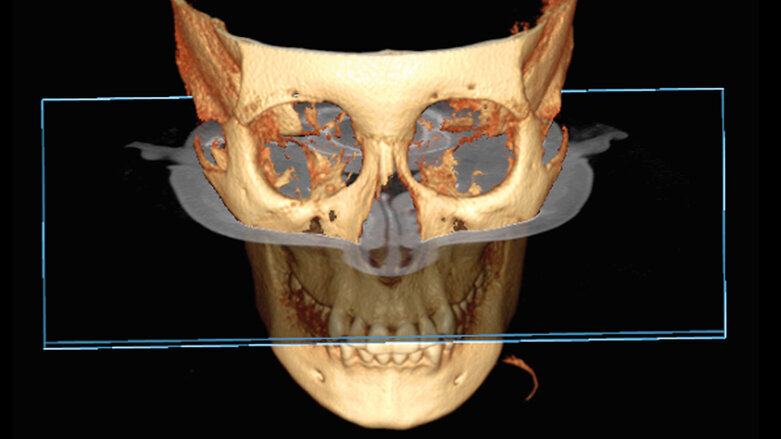

Koronální rovina (obr. 1, 2)

Koronální rovina je umístěna ve frontální části obličeje, probíhá víceméně rovnoběžně s vestibulárním povrchem předních zubů. Rozděluje lebku na dvě části: anteriorní a posteriorní. Struktury mohou být prohlíženy směrem dopředu nebo dozadu.